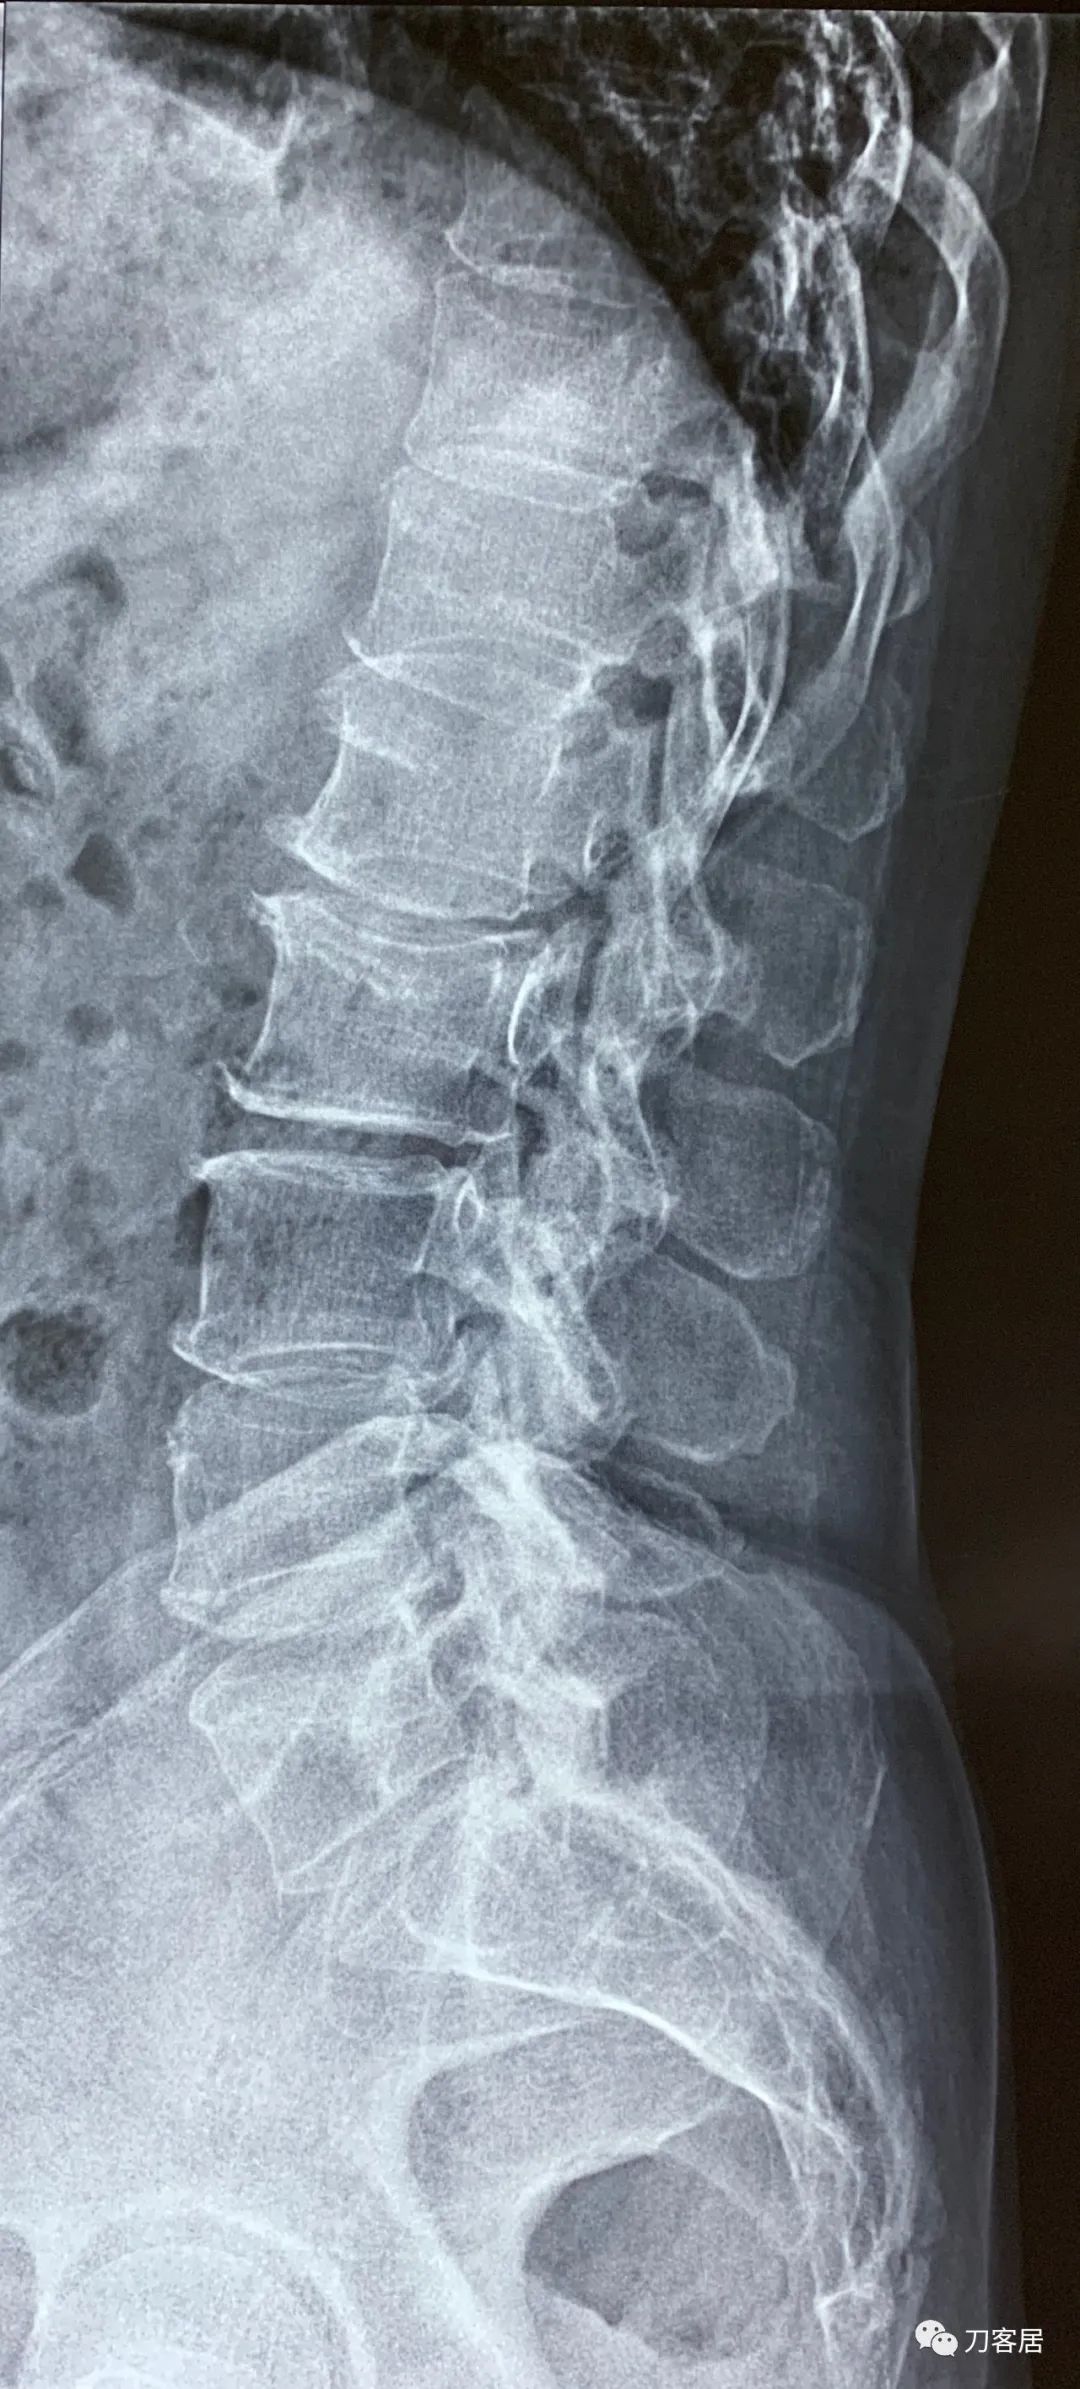

建议其查双光子骨密度,骨盆正位片以及腰椎间盘平扫。腰椎正侧位X线片以及动力位片,站立位脊柱全长正侧位X线片,以了解其是否有骨质疏松,并了解脊柱侧弯情况,腰椎局部X线表现情况和腰椎间盘突出和椎管狭窄情况。

从这个患者的影像资料分析,颈椎间盘突出问题不大,没有明确的上位神经元损伤表现,所以,不考虑颈椎和胸椎问题。腰椎侧弯畸形,但不严重。因为存在腰椎侧弯,使得腰椎MRI在扫描切面的时候,显示的椎间盘突出或椎管狭窄会有一定的误差,所以,又加做了经椎间盘的CT平扫,影像表现并不严重,综上,腰椎间盘突出,腰椎管狭窄,腰椎侧弯,不考虑手术治疗。同时,患者的主要痛苦是心理疾病,而不是器质性疾病,所以,以心身疾病治疗为主。虽然患者骨密度检查结果提示正常,但X线片显示骨质疏松,且其症状也与骨质疏松的症状有符合之处,比如静息痛,不能入睡,动作及姿势变换时痛加重等,所以,给予实验性抗骨质疏松治疗,以观疗效。

3. 2020年12月11日,在甘肃省中医院脊柱骨二科看病,吃中药,治疗半月,中途12月12日去渭源县医院做了核磁检查,提示腰椎侧弯畸形并骨质增生,腰5骶1椎体终板炎(I型), 腰1-骶1椎间盘变性并腰2-3,腰3-4,腰5骶1椎间盘膨出,腰4-5椎间盘突出并相应平面继发性椎管狭窄。